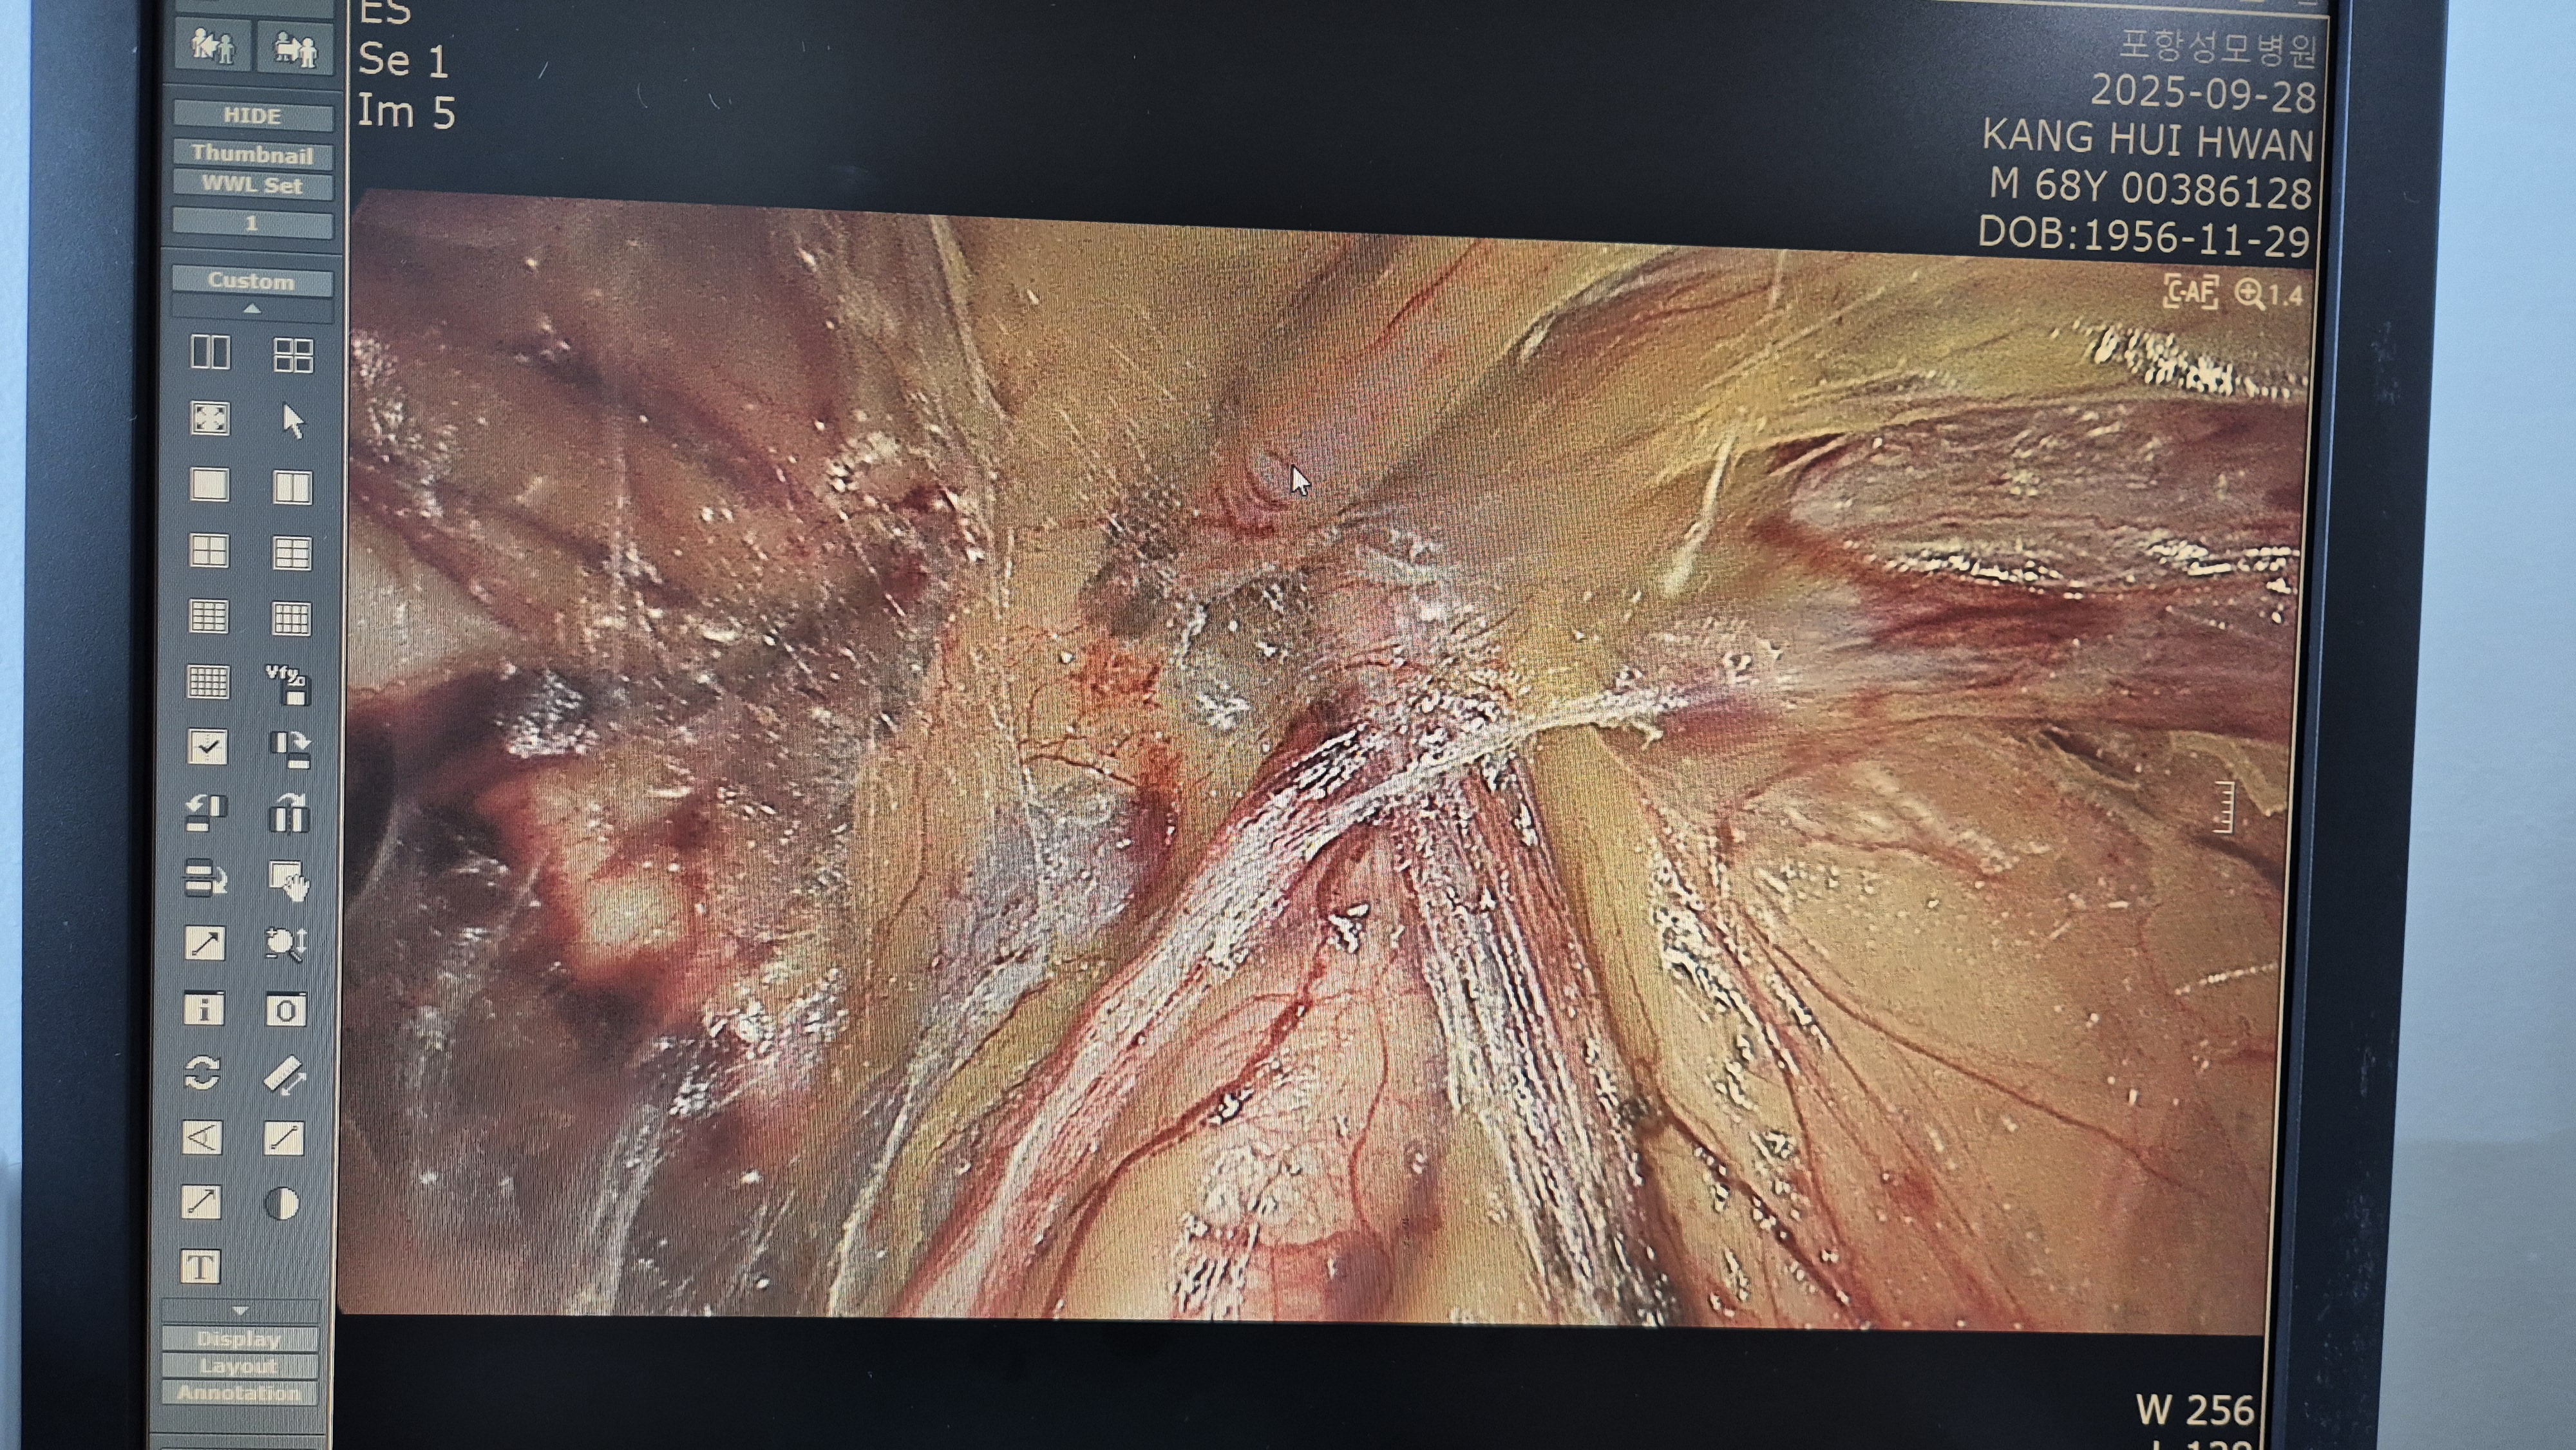

방금 복강경 탈장교정술을 시행했습니다.

탈장 확인후.

박리.

메쉬로 고정.

수술은 15분 걸렸습니다.